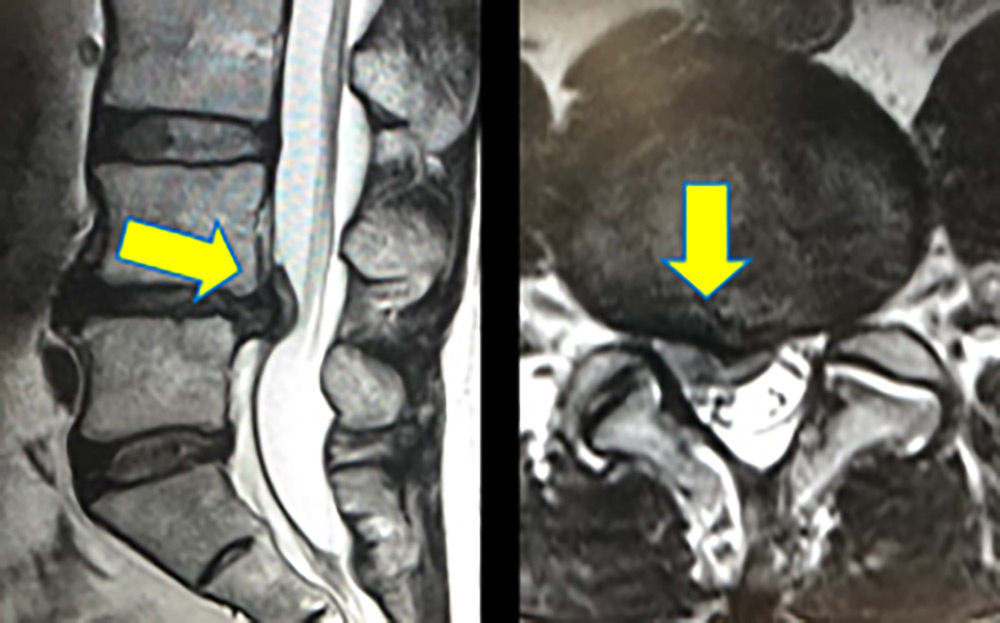

- MRI : 디스크의 위치와 상태를 정확하게 보여줍니다.